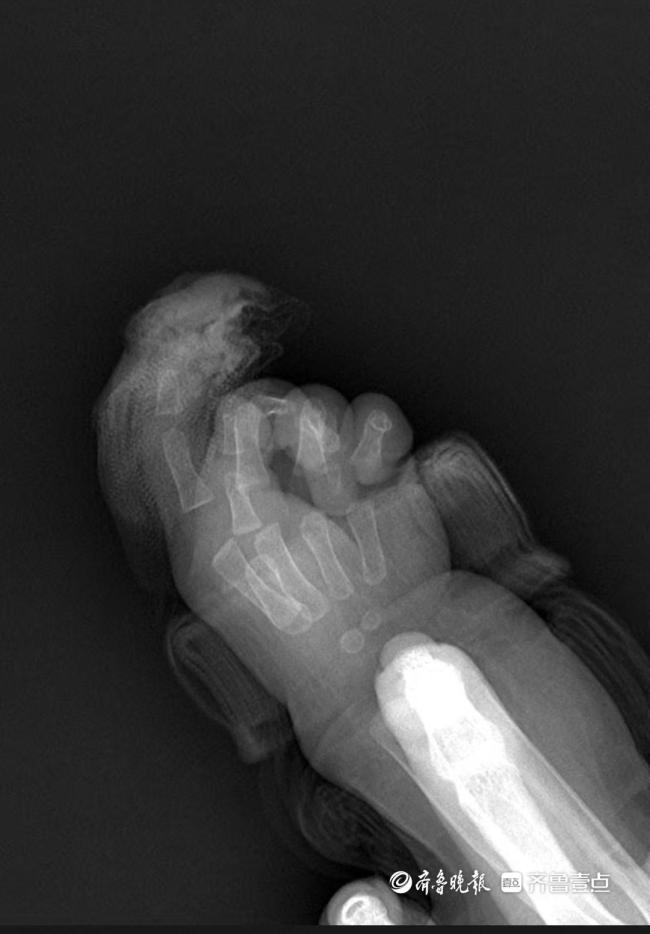

4月15日下午,在济南市第三人民医院手及上肢外科病房内,7个月大的芙芙正好奇地打量着周围,她的右手缠着厚厚的无菌纱布。11天前,这个刚萌出两颗乳牙的女婴经历了一场断指再植的极限救援——她的右手食指第一关节被剪刀完全剪断。

急诊就诊时间是9时22分,同步启动术前准备。手及上肢外科主治医生王思月回忆,急诊团队第一时间为芙芙止血、抽血、做心电图和拍片,“孩子伤口还在渗血,更换了3次纱布,同时输液,避免脱水。”